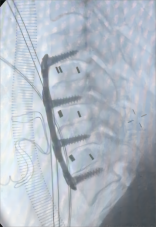

颈椎前路减压融合术适用于①屈曲型颈椎骨折或骨折脱位所致的颈椎创伤性不稳定;②颈椎爆裂性骨折,椎体粉碎,压迫脊髓或脊髓前动脉,产生脊髓前综合征,需做前路减压,解除脊髓受压。③后路广泛性椎板切除,颈椎不稳,经后外侧融合仍不牢固。目前我科已成功开展前路ACDF技术、ACCF技术、ROI-C插片技术、Zero-P零切迹技术,具有创伤小、恢复快、疗效佳,早期下床活动的优点。